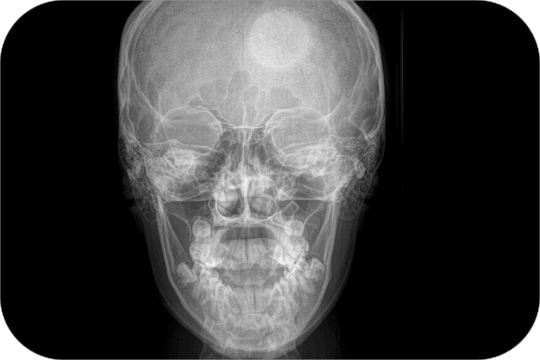

Antero Posterior

Postero Anterior